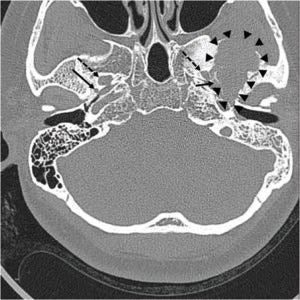

Figure 1. Pre-operative computed tomography showing a giant osteolytic lesion (margin indicated with arrow heads) contacting foramen spinosum (solid arrows), but not in contact with foramen ovale (dashed arrows).

A 46-year-old woman presented with persistent middle ear effusion and hearing loss on the left side. Pain during mastication started approximately five years prior and had recently gotten worse with trismus. She also presented with parageusia and a sour taste. Otoscopic examination revealed middle ear effusion on the left side, and she could not inflate the middle ear by Valsalva maneuver. A pure tone audiogram revealed conductive hearing loss on the left side. She underwent ventilation tube insertion in her left ear, but the tube was noted to have fallen out at an outpatient follow-up visit 30 months later, with recurrence of the middle ear effusion. There was no mass lesion on endoscopic nasopharyngeal examination. Therefore, Eustachian tube balloon dilatation was planned, and a pre-operative computed tomography (CT) scan was performed. High-resolution CT scans revealed a large, ill-defined osteolytic lesion with adjacent sclerotic changes in the left middle cranial fossa (Figure 1, arrowheads). Magnetic resonance imaging (MRI) showed the tumor did not contact the foramen ovale but was adjacent to the foramen spinosum and mandibular condyle. MRI showed an approximately 4-cm heterogeneous mass in the left temporal bone involving the sphenoid bone and left temporomandibular surface, growing downward into the infratemporal fossa. The mass appeared as an iso-and low-signal mixed lesion on pre-contrast T1-weighted images, and there was a markedly low signal within the tumor on T2 imaging with cystic changes. Post-contrast T1-weighted images revealed a heterogeneous enhancing lesion with intense enhancement of cystic areas, which is highly suggestive of a giant cell tumor. Positron emission tomography (PET) revealed a strong signal of high accumulation of 18F-fluoro-2-deoxy-D-glucose (18F-FDG) in the infratemporal fossa.